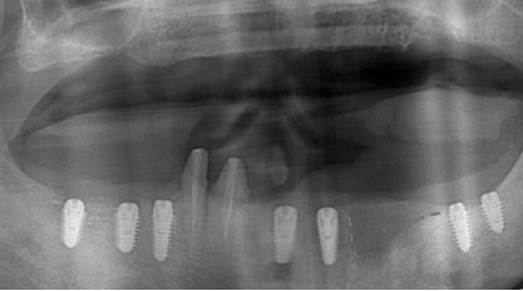

Clinical case: A Full transition from natural teeth to all-on-6 bridges

with AnyRidge implants

- Courtesy of Dr. Rabih Abi Nader, UAE -